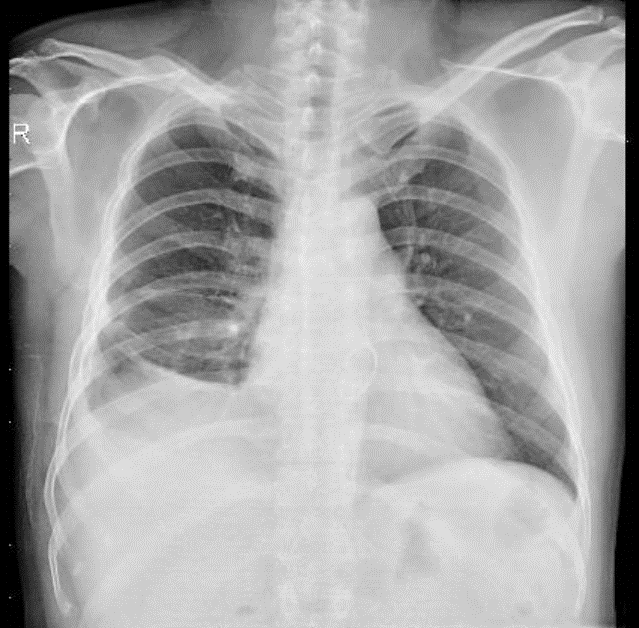

1-Thâm nhiễm lan tỏa thùy dưới phổi (P)=>Viêm phổi 2-Tràn dịch màng phổi (P) 3-Gãy cũ 1/3 giữa xương đòn(P)